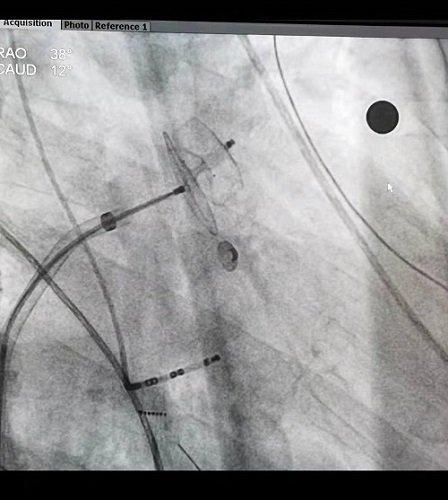

术中,张志辉教授带领罗文治主治医师及邓煦主治医师,首先对病人进行房颤的环肺静脉电隔离及左心房基质改良,随后应用心腔内超声,对患者的左心耳形态及直径大小进行了精确测量,结合X线下造影的影像,使用了ACP20mm的左心耳封堵器对患者左心耳进行封堵,封堵器到位顺利,一次性展开成形,再次应用腔内超声对展开后的封堵器进行测量,封堵器完美封堵左心耳开口,且对左心耳附近的结构没有影响,遂释放封堵器。整个手术过程患者均在清醒状态下,术中患者各项生命体征平稳。

X线下左心耳封堵器